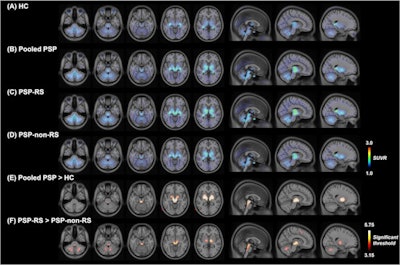

Liu's team sought to confirm findings from these preclinical studies in a large group of patients using PET imaging with F-18 Florzolotau, a tracer originally developed in 2020 that has shown promise for detecting hallmark tau pathology in Alzheimer's disease. To do so, the investigators recruited 148 consecutive patients with PSP to undergo F-18 Florzolotau PET imaging between May 2019 and January 2022. Twenty subjects with a negative history for neurological or psychiatric disorders were included in a control group for comparison. The researchers tracked 18 subcortical regions of interest and eight cortical regions of interest.

Based on standard radiotracer uptake measurements, the distribution patterns of F-18 Florzolotau uptake in the regions of interest showed a striking similarity to those reported in postmortem studies, with the binding intensity of the tracer to its tau target markedly higher in PSP-/Richardson's syndrome, the classic type of PSP. The tracer also detected tau accumulation at earlier stages of the disorder compared with postmortem immunostaining findings, they noted.